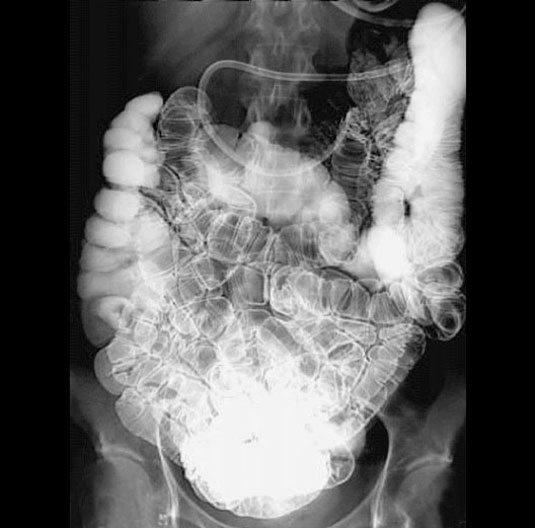

Enteroclysis

1. Ileum

2. Ascending Colon

3. Right Colic (Hepatic) Flexure

4. Catheter

5. Transverse Colon

6. Jejunum